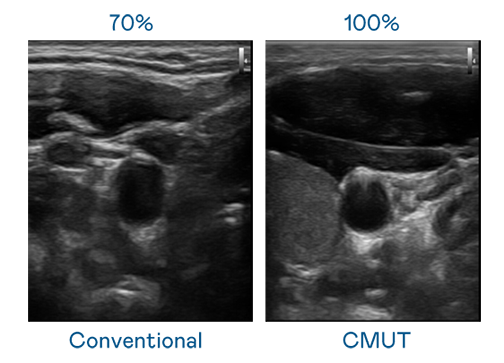

CMUT 技术是一种用电容式微机电元件来产生超音波讯号的技术。与传统 PZT 压电式技术相比,CMUT 频宽增加 30%,更宽频的超音波讯号让影像解析度大幅提升,是实现高影像品质医疗超音波扫描、促进精准医疗发展的关键技术。

大频宽带来超清晰影像

超音波影像的解析度高低,首先取决于探头能发出的讯号频宽。4556银河国际 CMUT 可提供高清晰的超音波讯号,提供高频宽、高灵敏度、影像纹理细节更高的超音波影像,协助医护人员缩短影像判读时间及利用精准的医疗影像进行诊断。